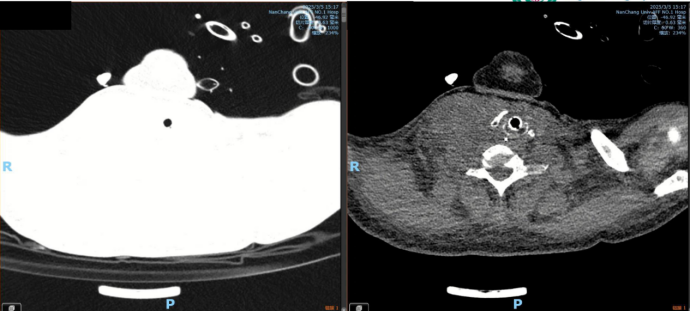

医生安排了胸部CT。报告出来的那天,我被单独叫进诊室。医生指着片子说:“您爱人情况很严重,肺部有一个很大的占位,考虑是恶性肿瘤,可能已经转移。

图源患者本人提供

2025年3月3日,我带妻子来到南昌大学第一附属医院。这一天,我终生难忘。就在影像科门口排队等待增强CT时,她坐在椅子上脸色越来越白,嘴唇突然发紫,大口喘气,接着在我眼前昏了过去。医生护士飞奔而来,迅速插管、上呼吸机,将她推进了重症监护室。

出院后,妻子每天按时口服伊鲁阿克。生活仿佛重回轨道,却又处处不同。最明显的是她身体的变化服药一个月后复查,CT显示肺部肿瘤缩小一大半,颈部的肿块也完全摸不到了。崔医生对着片子连连点头:“效果非常好。”

图源:患者本人提供